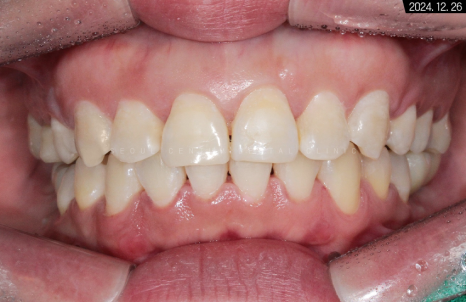

유지장치를 부착하고 난 후의 악궁 사진입니다.

수평 피개가 해소되었기 때문에

측면에서 봐도 중심선이 바릅니다.

둥글게 변하면서

교합 상태가 이상적인 모습을 보이네요.

세팔로 사진으로 보면 전돌 해소가

더 확실하게 된 것을 볼 수 있어요.

에스테틱 라인도 좋아지고

전체적으로 부드러워진 비율이 나타나고 있습니다.

입술이 예전보다 슬립한 형태가 되기도 하셨고요.